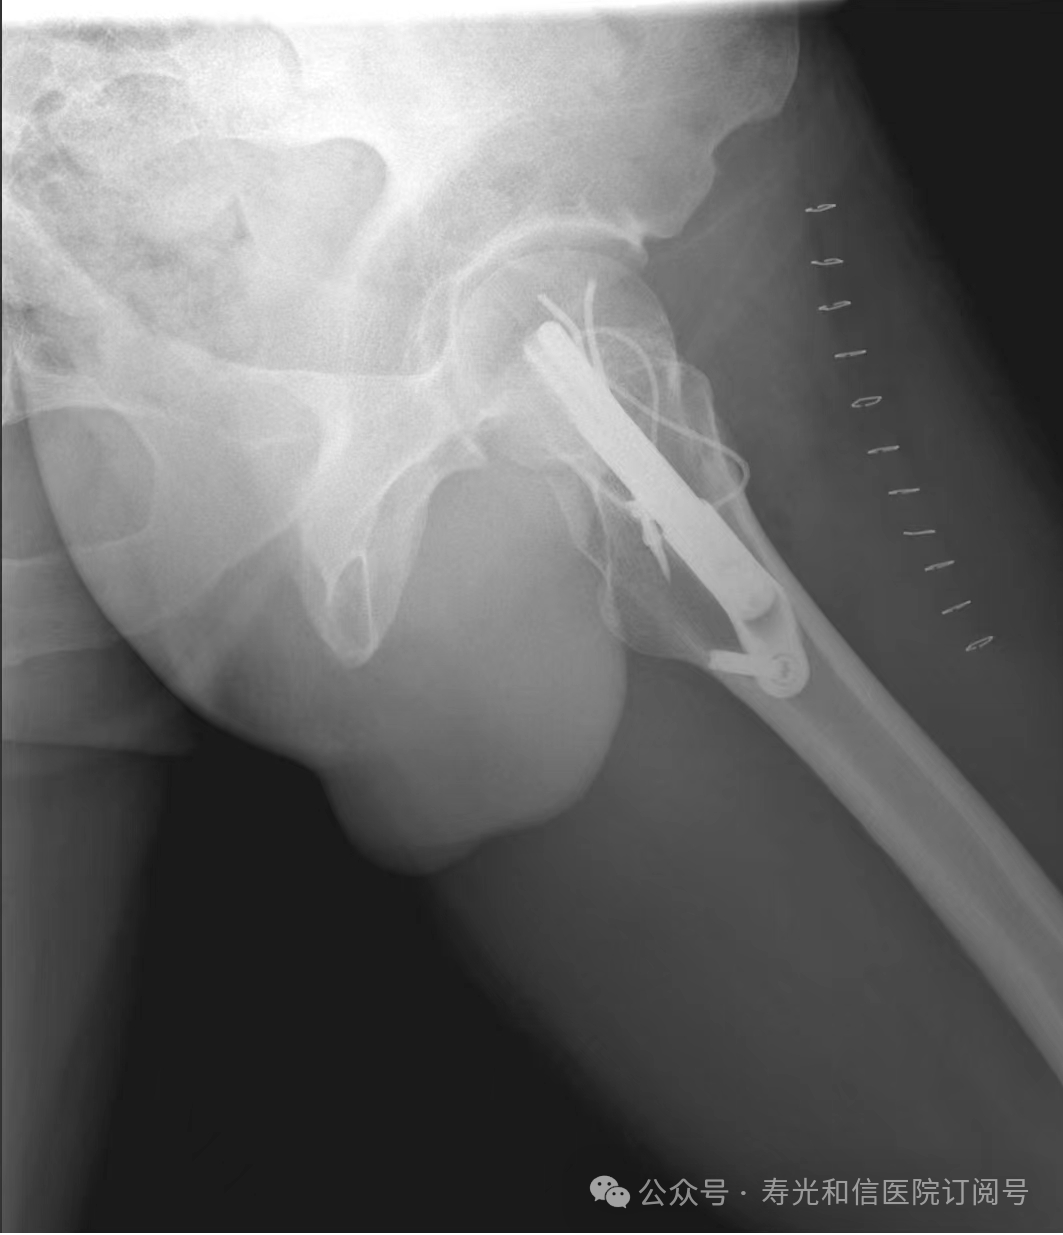

患者经120接诊,完善相关辅助检查后收入寿光和信医院骨外科。检查发现,患者右锁骨骨折、左股骨颈骨折、左大转子撕脱骨折、右膝关节前交叉韧带止点撕脱骨折、右膝关节外侧副韧带损伤、颅骨骨折及全身多处皮肤挫伤。因患者是外地来寿人员,家属短时间内不能赶过来,并且患者家庭经济条件较差,没有缴纳住院手术费的能力。但是股骨颈骨折后,股骨头坏死发生几率较高,手术越早进行,越有利于减少发生股骨头坏死的几率。骨外科主任李刚始终牢记救死扶伤的神圣职责,本着为病人负责的原则,坚定地选择先行为患者实行手术治疗。

与患者本人充分沟通后,李刚主任率领骨外科团队,经过充分的术前讨论及术前准备,于2024年9月1日为患者在全身麻醉下实施了4个半小时的内固定手术治疗。“时间就是生命”,手术过程中,全体参与人员密切观察病情变化,敏锐发现早期异常指标,争分夺秒,一丝不苟地做好各项抢救救治工作,做到瞬间判断、正确评估、果断处理,赢得了抢救患者的“黄金时机”,确保了手术的顺利完成。

在为其进行股骨颈骨折治疗时,手术团队为其采取了股骨颈动力交叉钉系统,这是一种新型股骨颈内固定系统,属微创植入,较从前的技术具有手术时间短、创伤小、力学稳定、滑动加压等优点。同时,患者恢复快,可早期离床、不负重下活动,缩短住院时间及康复时间,有效降低患者股骨颈骨折不愈合发生率,降低长期卧床合并症和死亡率。